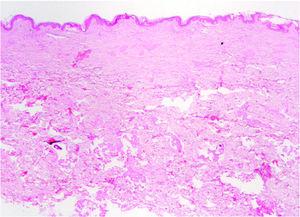

Fig. 3.--Biopsia de placa en espalda. Marcada fibrosis en dermis papilar y reticular superficial. (Hematoxilina-eosina, ×20.)

Se tomaron varias muestras para estudio histopatológico, de la espalda en el momento de la primera visita (fig. 3) y de la ampolla de la región pretibial derecha (fig. 4).

HISTOPATOLOGIA

En la biopsia de la placa de la espalda (fig. 3) se observa un fragmento de piel con discreta hiperqueratosis y de forma más significativa, una marcada fibrosis en forma de haces colágenos gruesos dispuestos de forma compacta en la dermis papilar y reticular más superficial; asimismo se observan ligeros infiltrados perivasculares de células redondas. No hay alteraciones en dermis profunda ni en el tejido celular subcutáneo.